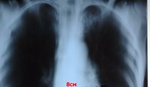

Ожидаемое. Рентгенолог см. рентгенорамму, видит что-то невнятное на верхушке, фиброз не фиброз. На дообследование вызвать? А, это будет R+!

По злобности моего характера, невзирая на возражения и "посмотрим в динамике", уговорил лаборанткуsmiley( не мой кабинет!) сделать томограммы.

Туберкулез ?

Не ожидал.Чуть мимо не прошёл.Туберкулёз,похоже."И ты,Брут?Не ожидал.Сюрприз".

Не работает, местная, БК+ точно уже. Скопия многократно + есть рост.sad

Но где же большая полость откуда такой камнепад?

Размеры полости не коррелируют напрямую с объёмом бацилловыделения.

Вот-вот, еще интереснее скажу-ее вообще можно не найти, а МБТ будут. Догадайтесь, откуда.

Из бронха.При туб. бронха.